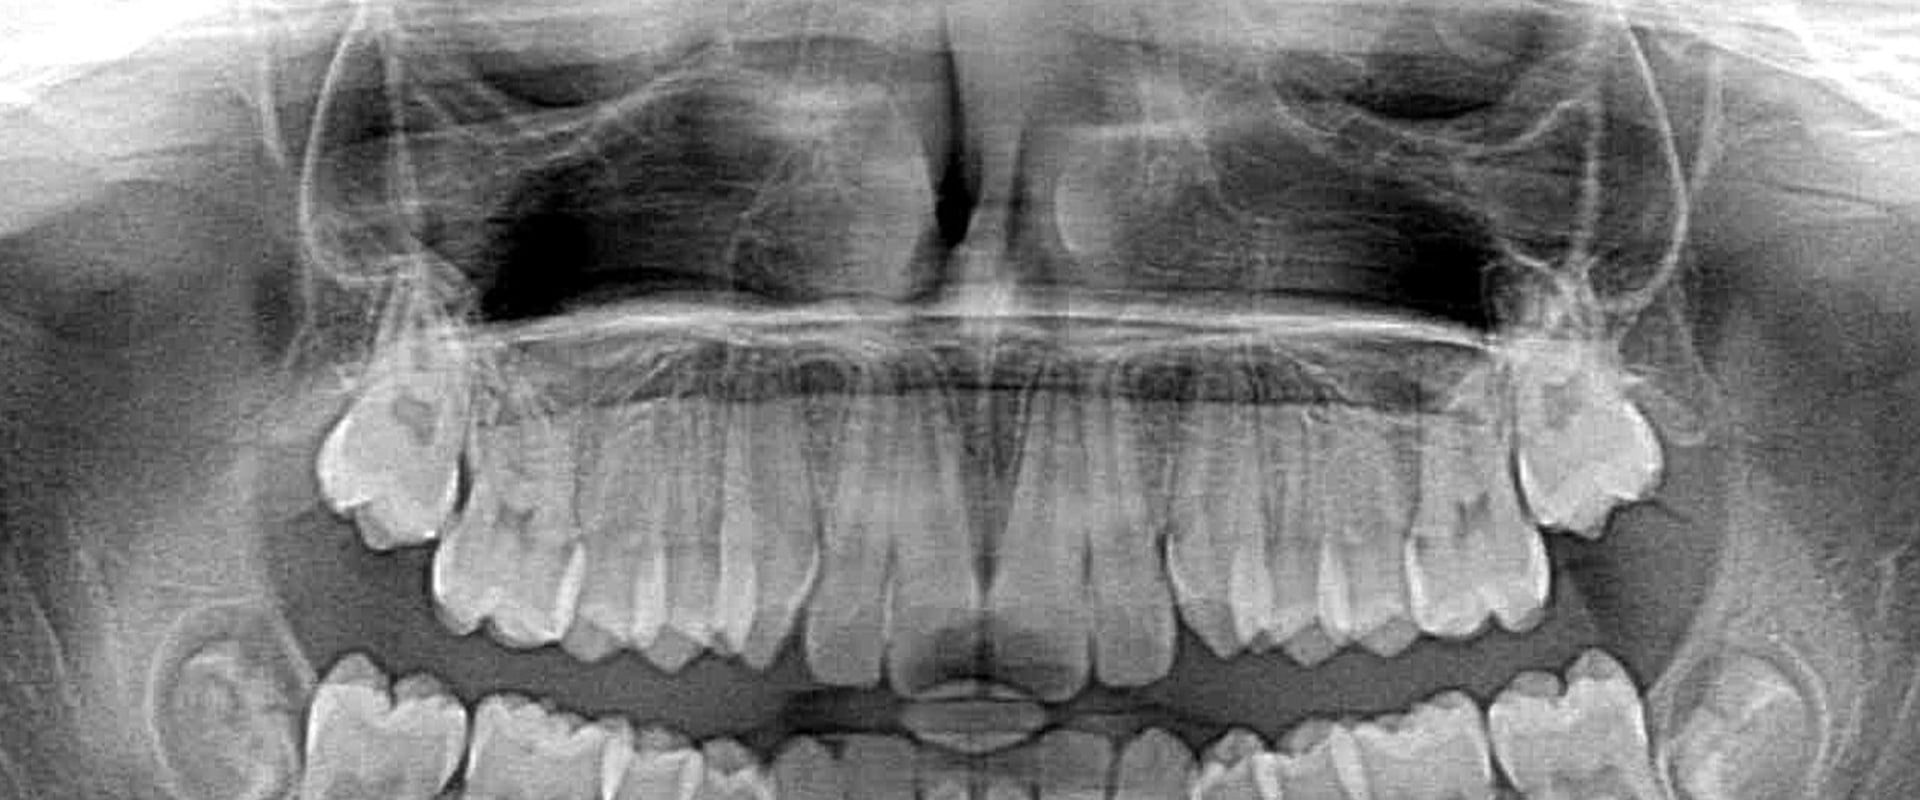

dental xrays Panoramic xray Hancock Village Dental